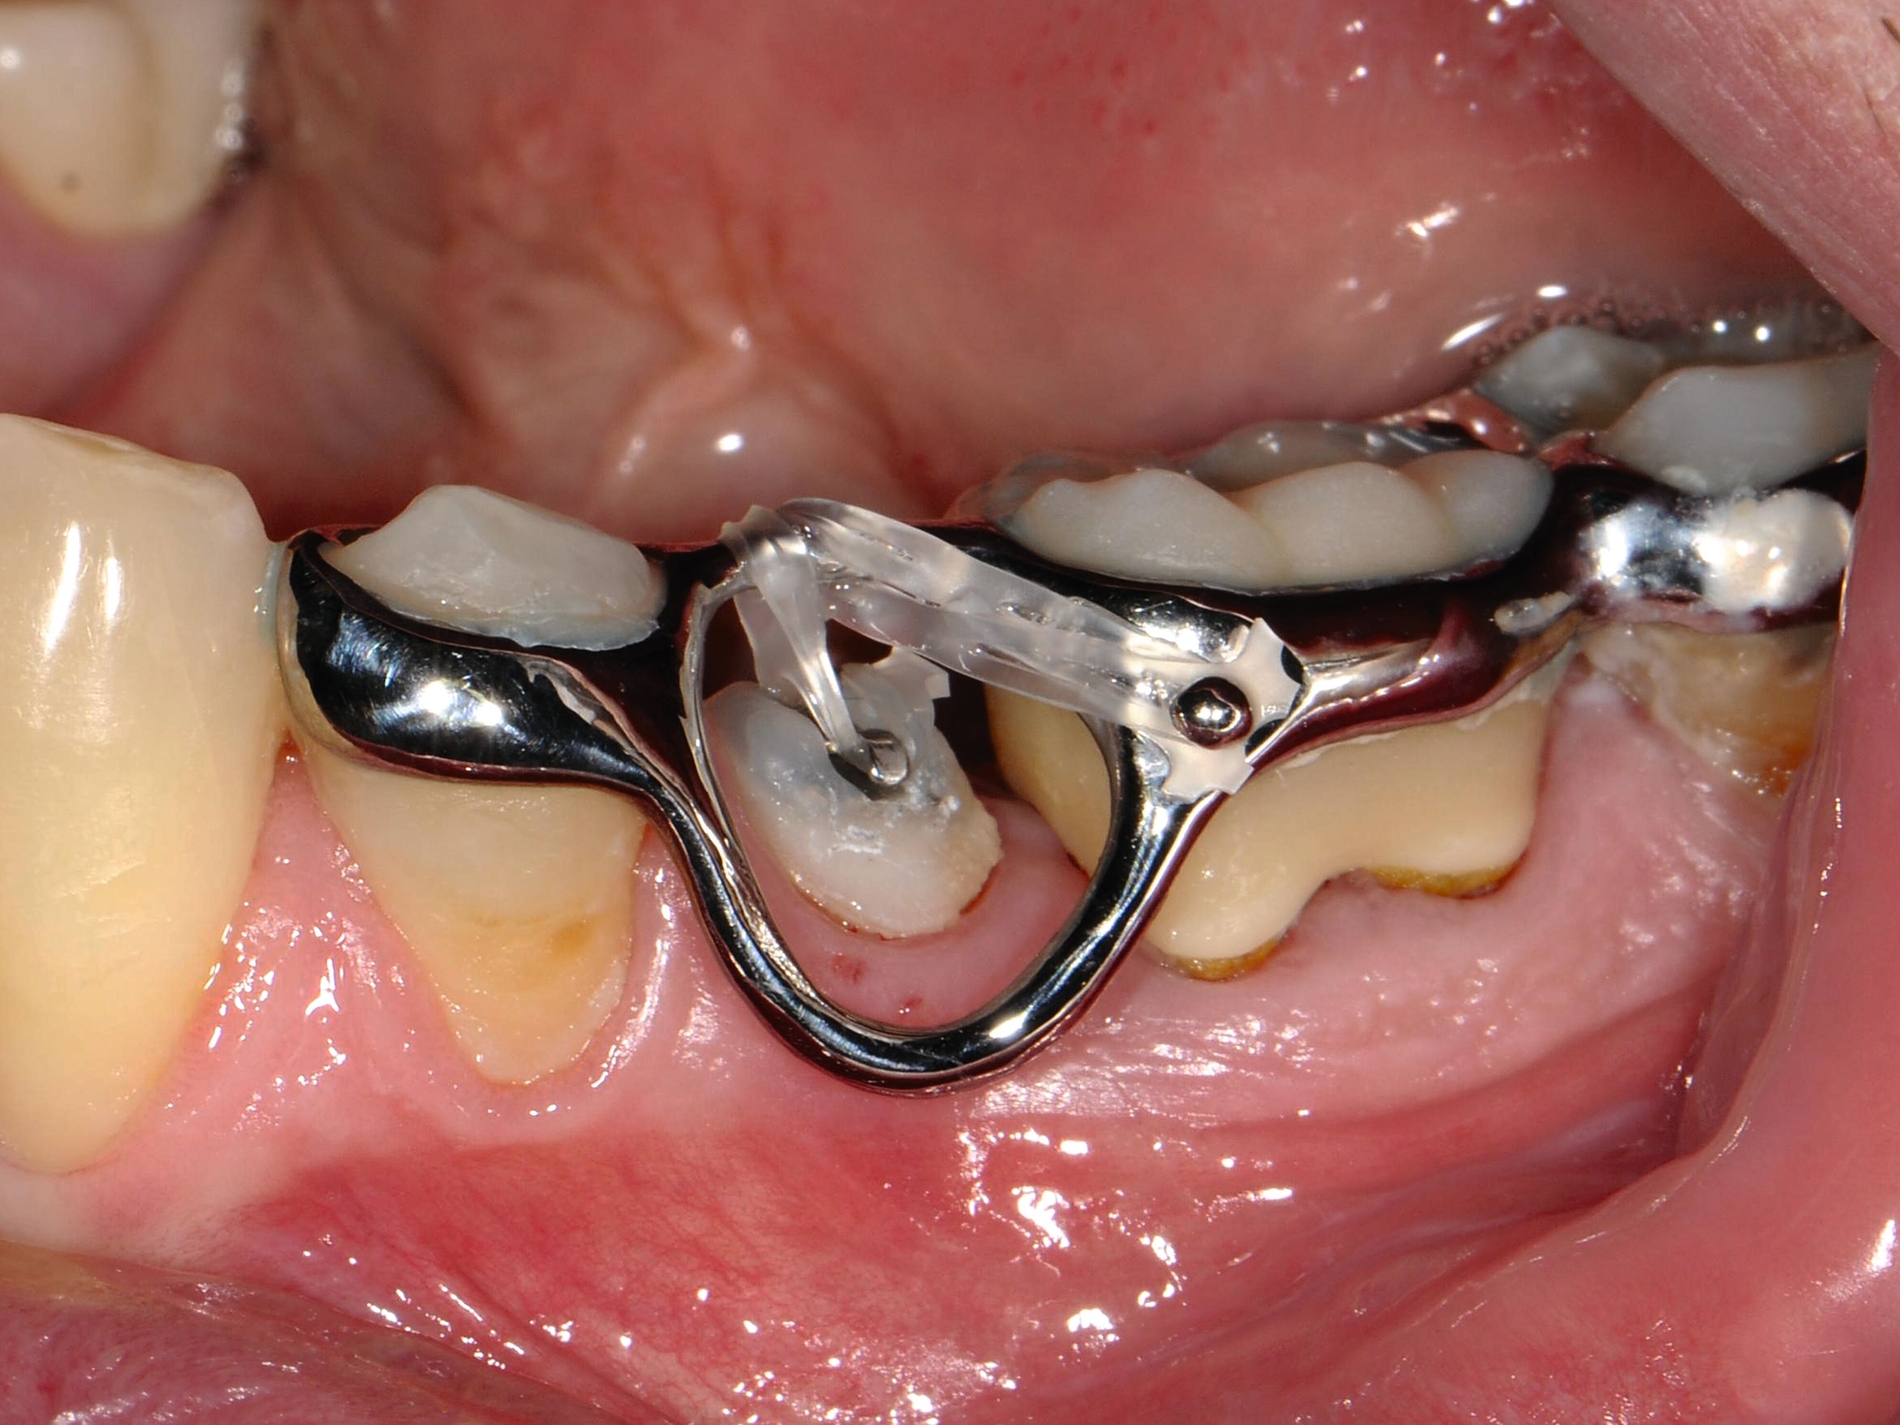

Schnelle kieferorthopädische Extrusionen im Sinne einer präprothetischen Maßnahme können zudem auch im Seitenzahnbereich indiziert sein, wenn für eine nachfolgende Kronenversorgung die notwendigen Voraussetzungen geschaffen werden sollen (ausreichende Stumpfhöhe, Einhaltung der biologischen Breite, Schaffung des Ferrule-Designs) [Gariulo et al., 1961; Juloski et al., 2012; Nugala et al., 2012] unter Einhalten eines Kronen-Wurzel-Verhältnisses von 1:1 [Grossmann und Sadan, 2005] (Abbildung 3).

Durch den Einsatz skelettaler Verankerungshilfen ist es möglich, auch in komplexeren Situationen einen kieferorthopädischen Lückenschluss durchzuführen. Mit digitalen CAD/CAM-Herstellungsmethoden wie dem selektiven Laser-Melting-Verfahren können hochindividualisierte Apparaturen angefertigt werden, die verschiedene Behandlungsaufgaben gleichzeitig adressieren beziehungsweise mit deren Hilfe Kraftvektoren präzise geplant und appliziert werden können.

Zu den weiteren Vorteilen gehören die geringeren Nebenwirkungen auf die Nachbarzähne, die bessere Planbarkeit bei Set-up-basierten Apparaturen, die gute Pflegbarkeit, die einfache Handhabung, die Verkürzung der gesamten Behandlungszeit durch reduzierte Multibracket-Phasen sowie die geringere Beeinträchtigung der orofazialen Ästhetik (Abbildung 5).

Bei Kronen-Wurzel-Frakturen beziehungsweise zervikalen Wurzelfrakturen kann geprüft werden, ob durch schnelle kieferorthopädische Extrusionsmaßnahmen eine nachfolgende Restauration des betroffenen Zahnes wieder ermöglicht wird. Langsame Extrusionen hingegen werden häufig zum Gewebeaufbau oder zur Einstellung eines geeigneten Gingiva- oder Knochenverlaufs eingesetzt. Digital geplante Laser-Melting-Apparaturen ermöglichen es hier, die notwendigen Kraftvektoren besonders präzise bei geringer Stuhlzeit am Patienten anzuwenden.